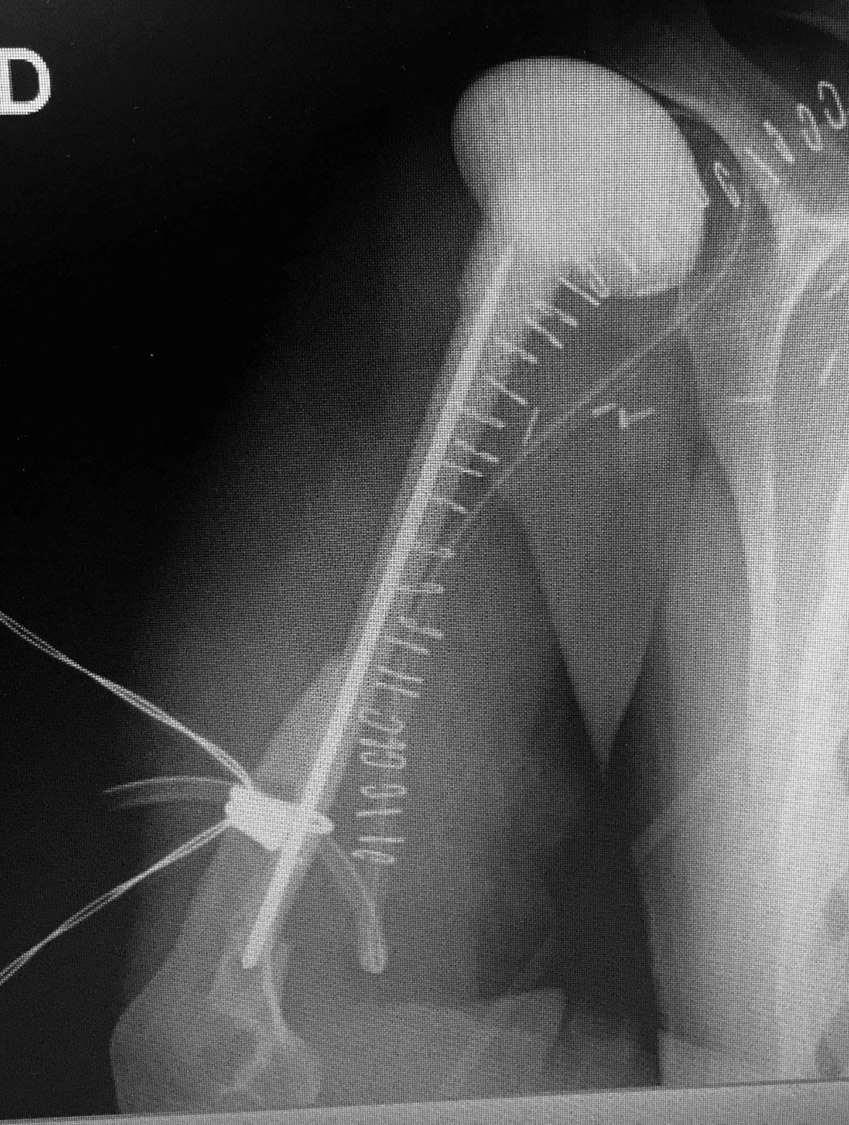

Defecto humeral masivo por prótesis oncológica infectada: reconstrucción con peroné microvascular

Paciente de 25 años que acude por defecto óseo masivo de húmero y hombro tras retirada de megaprótesis oncológica. La mano y el codo son funcionales pero el defecto óseo impide por completo cualquier función de la extremidad.

Se reconstruyó el húmero con colgajo microvascular de peroné tallado para optimizar la fusión del hombro.